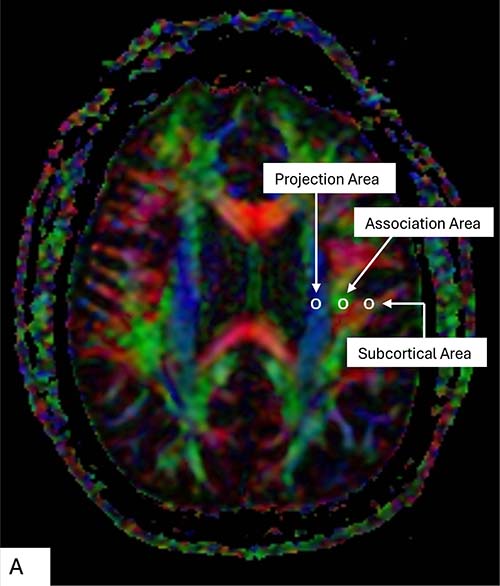

Figure 1. (A) Color display of diffusion tensor imaging indicating the distribution of projection fibers (z-axis: blue), association fibers (y-axis: green), and the subcortical fibers (x-axis: red). Three regions of interest are placed in the area with projection fibers (projection area), association fibers (association area), and subcortical fibers (subcortical area) to measure diffusivities of the three directions (x, y, z). (B) Schematic indicating the relationship between the direction of the perivascular space (black lines) and the directions of the fibers.

Figure 2. Color display of diffusion tensor imaging indicating the distribution of projection fibers (z-axis: blue), association fibers (y-axis: green), and the subcortical fibers (x-axis: red). Three regions of interest are placed in the area with projection fibers (projection area), association fibers (association area), and subcortical fibers (subcortical area) to measure diffusivities of the three directions (x, y, z).